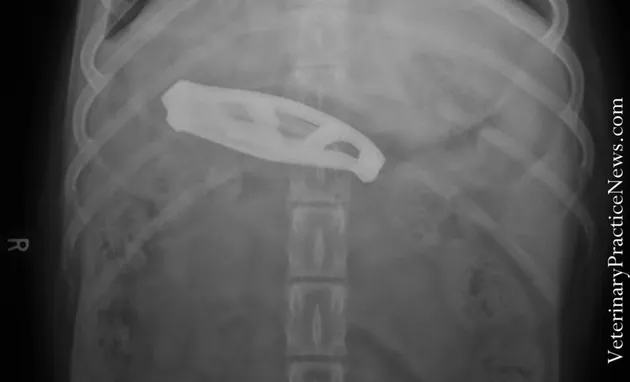

Seekor anjing yang bernama Lucy tak senagaja menelan pisau mini yang diletakkan di meja makan. Sang pemilik pun akhirnya memberikan obat perangsang kepadanya sehingga Lucy mual dan memuntahkan pisau tersebut.

Hak Cipta: Veterinary Practice News